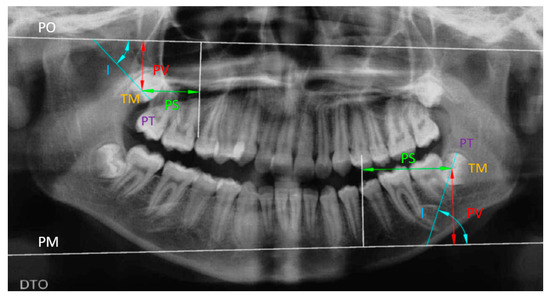

Pre- and post-treatment digital panoramic radiographs were taken for each patient. All radiographs were taken using the same machine (Gendex Orthoralix 9200 DDE, Gendex Dental Systems, Des Plains, IL, USA). Radiographic analysis was performed using Auto CAD 2021 for Window. Landmarks and planes used in Tavano method [11] were determined on each panoramic radiograph (Figure 1). An intra-examiner reproducibility study was undertaken on eight panoramic radiographs by repeating the tracing after two weeks by the same operator. The results confirmed an excellent agreement between the two trials for all the variables (≥95%).

Figure 1. A panoramic radiograph illustrating the different reference planes used in determining the position of the maxillary and mandibular third molars: PO = Orbital plane, PM = Menton plane, PT = Transversal plane, TM = Midpoint of the longest mesio-distal distance of the third molars, I = Inclination, PS = Sagittal position, PV = Vertical position.